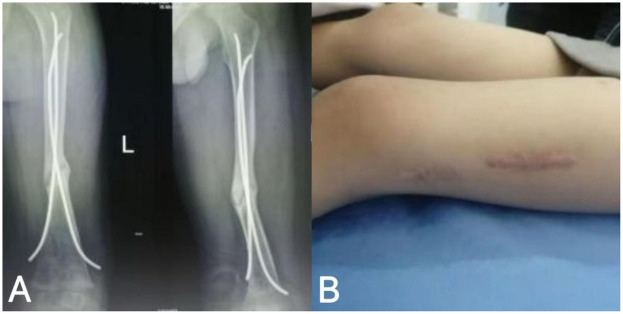

Methods: A 4-year-old male with left femoral shaft fracture (AO/OTA 32A2) and FDA-defined nonunion 9 months after FIN fixation received rESWT. Using Gymna ShockMaster 300 (Uniphy), parameters were 6-8 Hz, 2.0-3.0 bar, 1,000-1,500 pulses/week for 3-4 weeks (covering fracture and 2 cm around). Treatment included pre-procedural screening, professional operation, gamified communication, and concurrent rehabilitation.

Results: Post-rESWT, fracture lines blurred then disappeared, with clinical healing achieved and no complications. At 3-month follow-up, intramedullary nail was removed; the patient had 80% weight-bearing capacity, independent walking (mild gait asymmetry), and full weight-bearing recovery later.